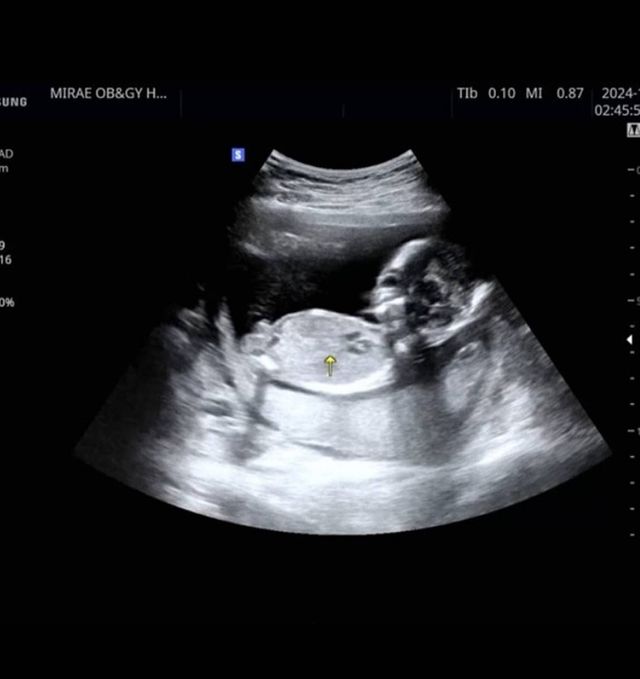

배우 전성초가 올린 초음파 사진 / 전성초 인스타그램

배우 전성초가 임신 소식을 전했다. 유산의 아픔을 겪은 지 1년 만이다.